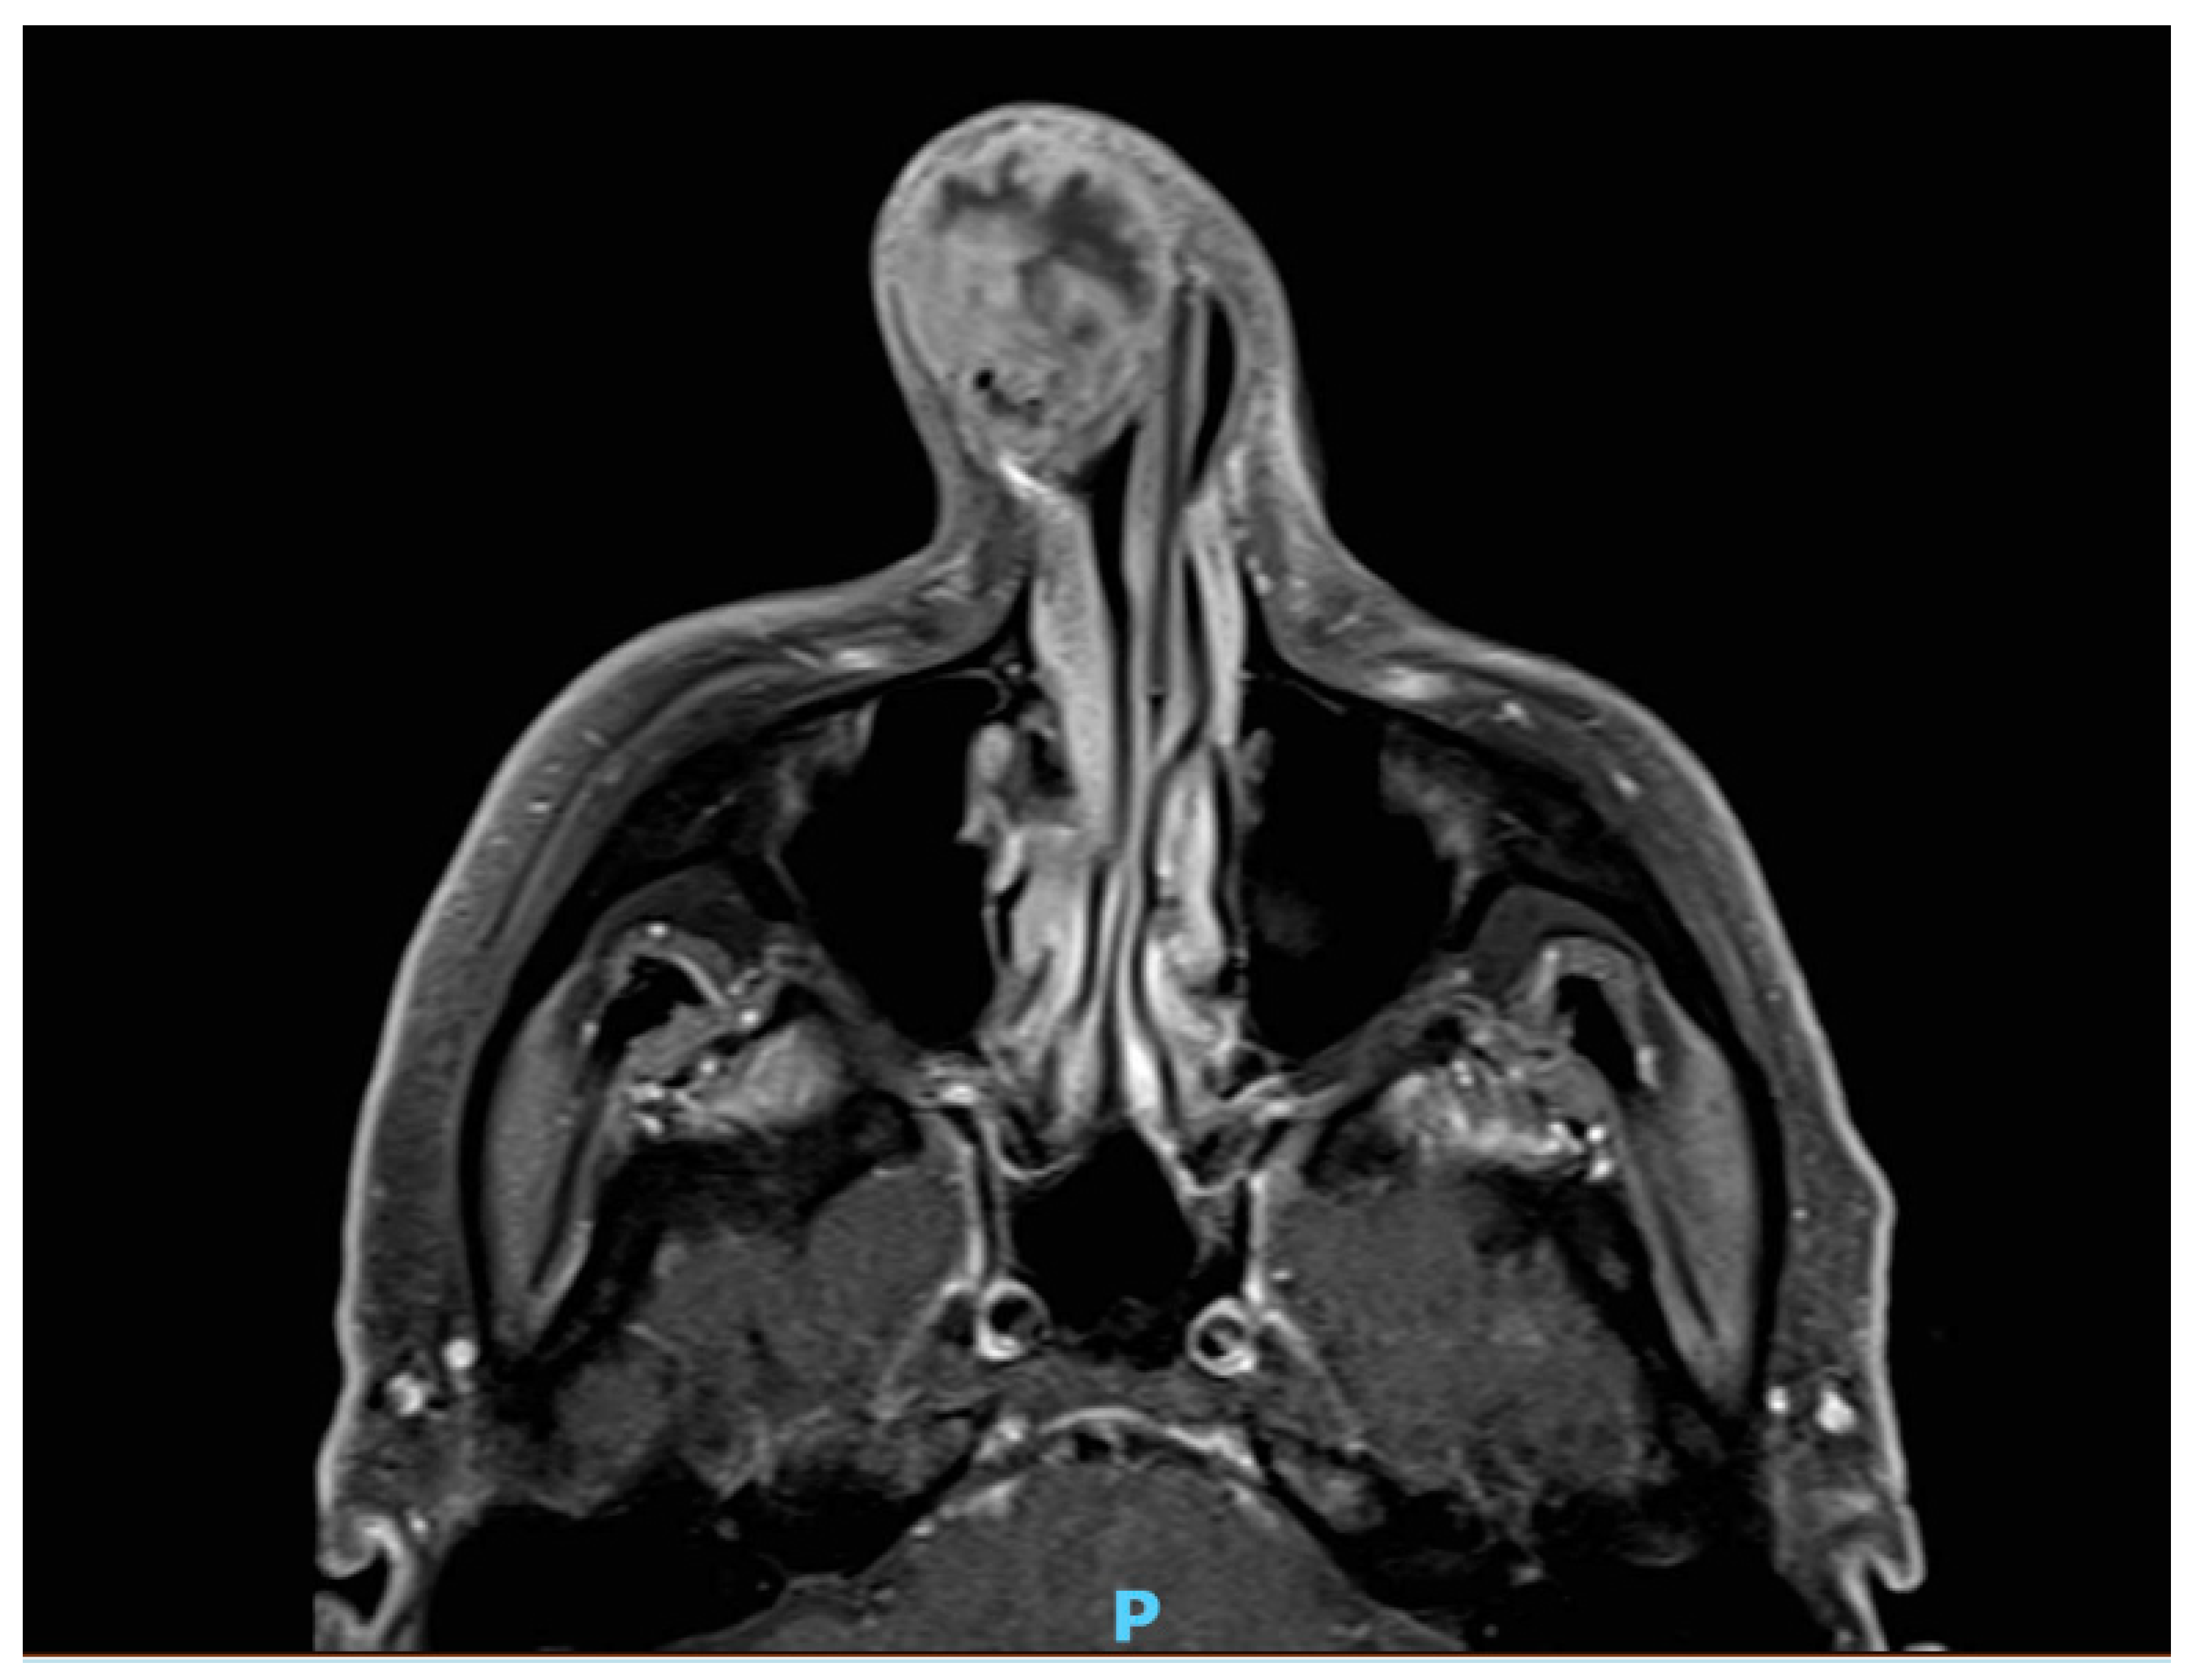

Nasal Chondrosarcoma of the Lower Lateral Cartilage

2. Case